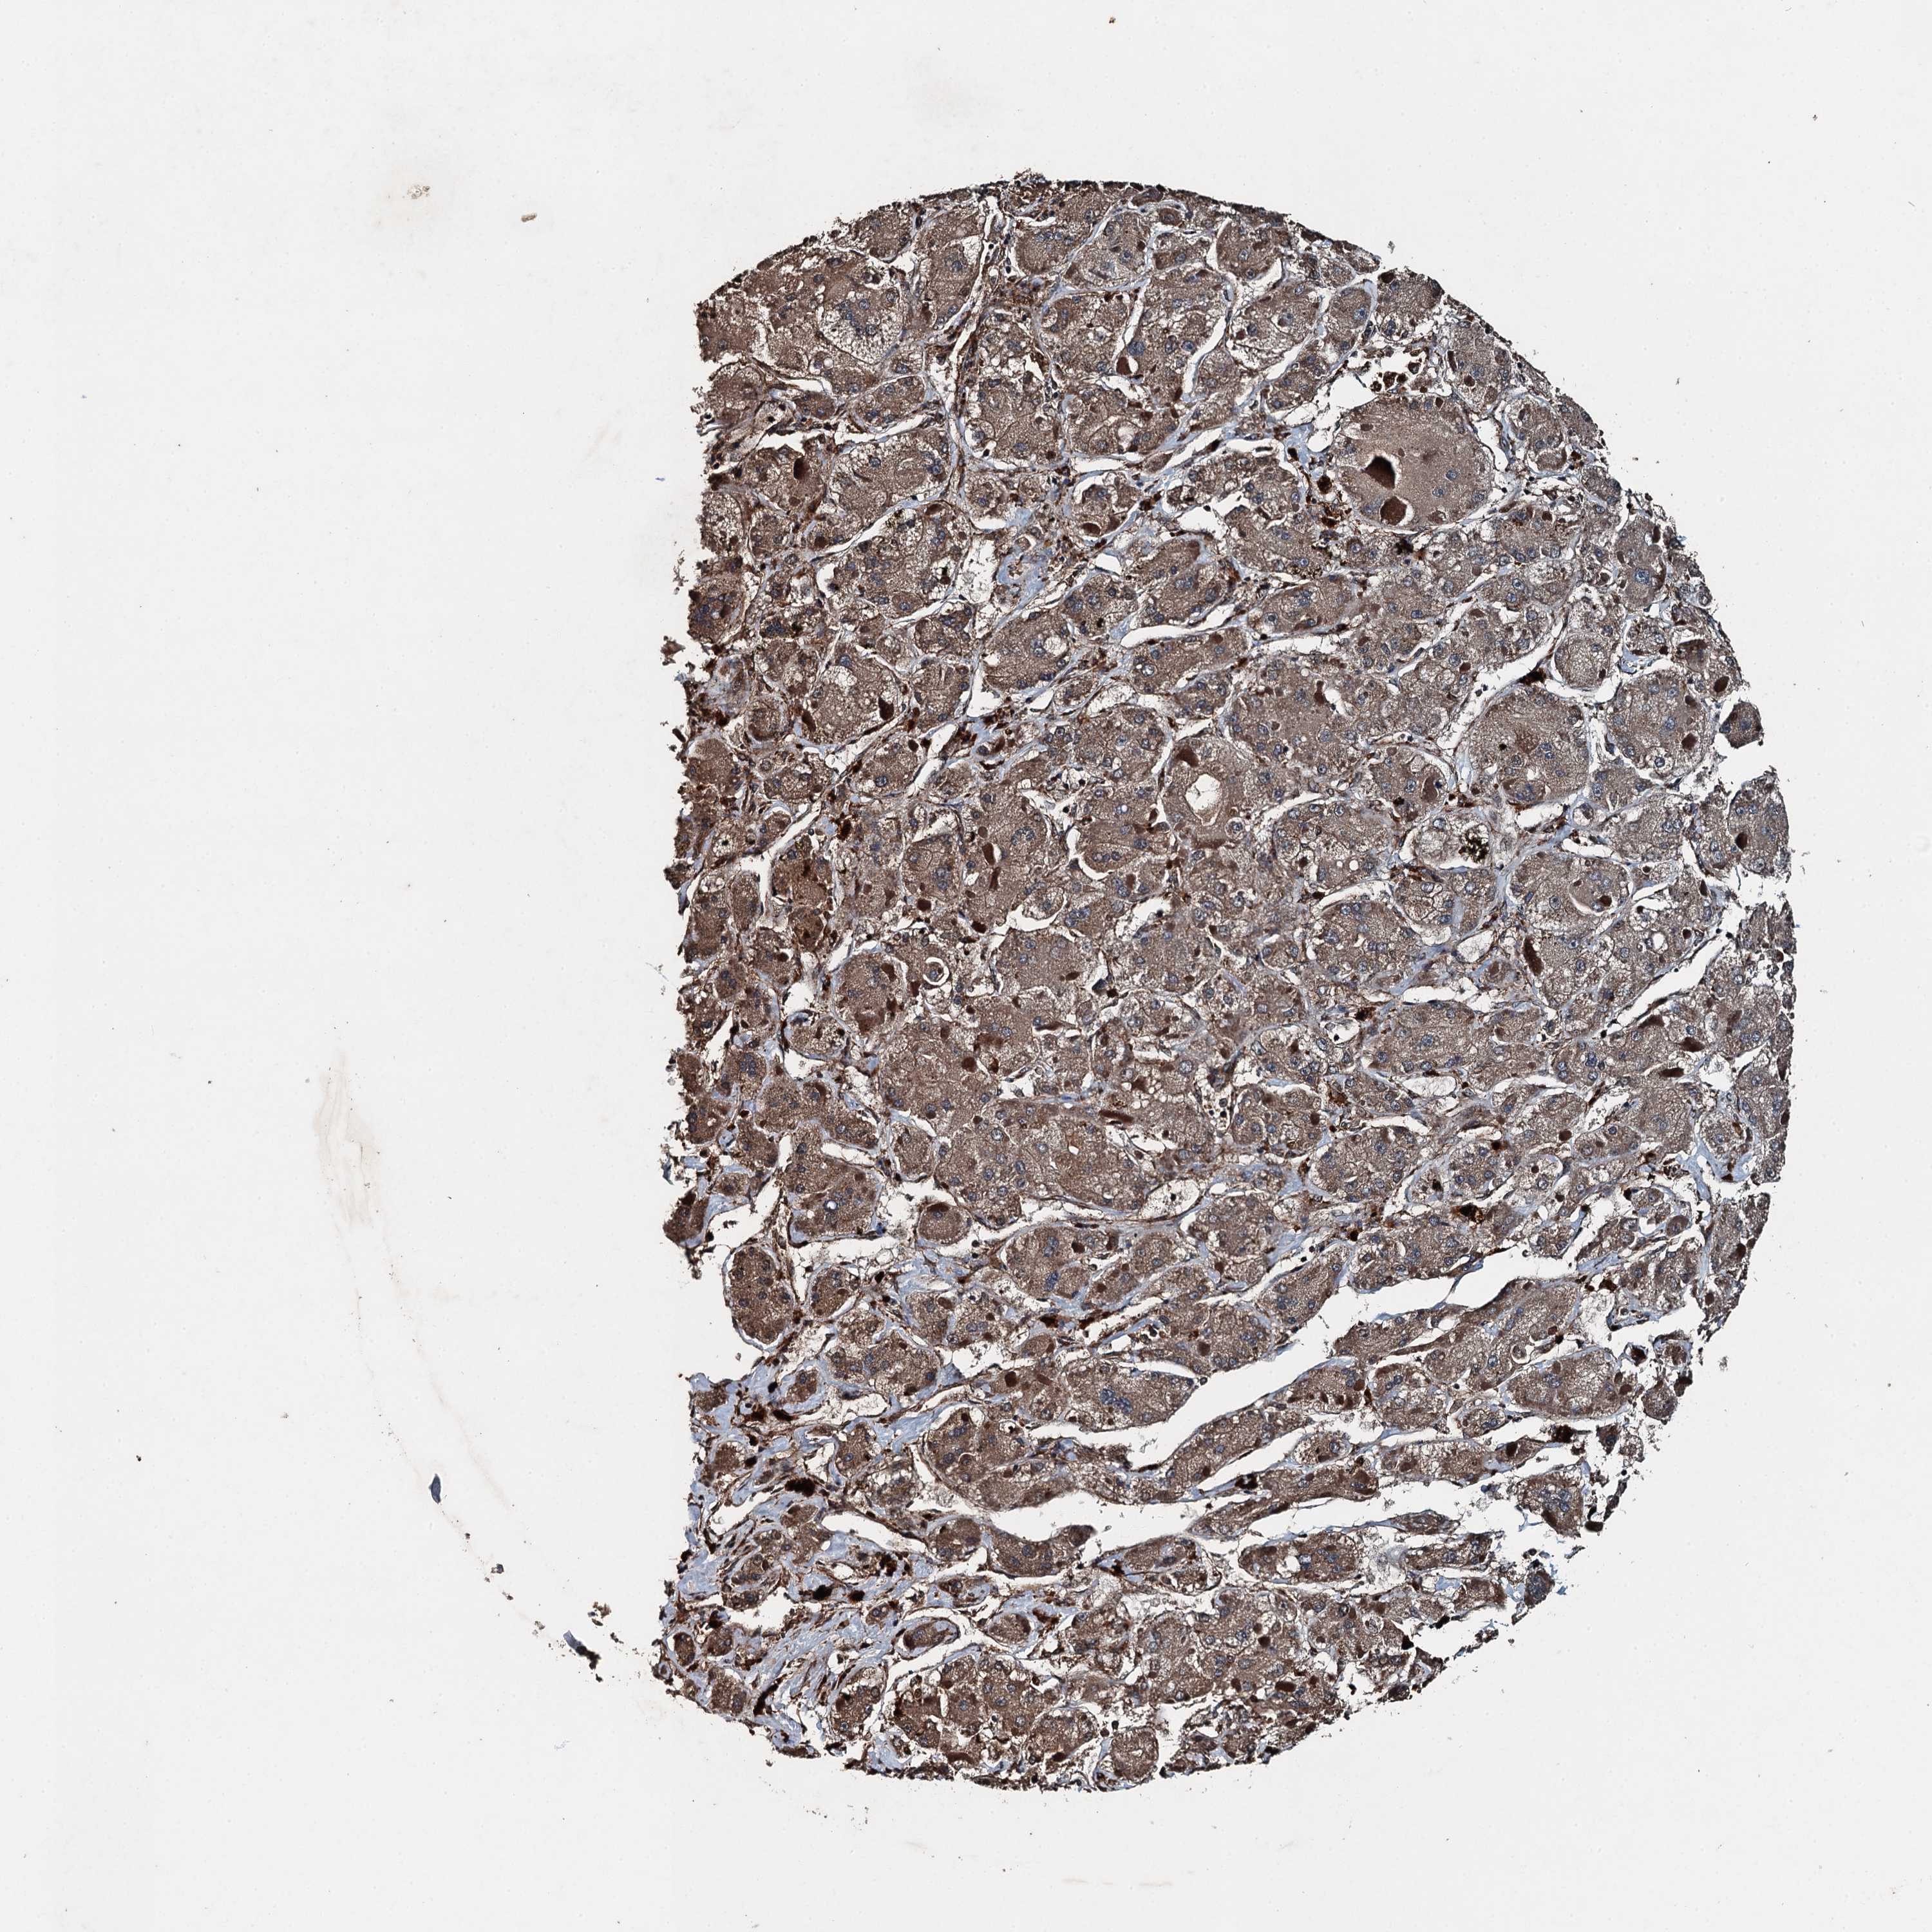

LIVER CANCER - Protein expressioni

A mouse-over function shows sample information and annotation data. Click on an image to view it in a full screen mode. Samples can be filtered based on level of antibody staining by selecting one or several of the following categories: high, medium, low and not detected. The assay and annotation is described here.

Note that samples used for immunohistochemistry by the Human Protein Atlas do not correspond to samples in the TCGA dataset.

Antibody stainingi

Antibody staining in the annotated cell types in the current human tissue is reported as not detected, low, medium, or high, based on conventional immunohistochemistry profiling in selected tissues. This score is based on the combination of the staining intensity and fraction of stained cells.

Each image is clickable and will lead to virtual microscopy that enables deeper exploration of all samples and also displays staining intensity scores, fraction scores and subcellular localization as well as patient and tissue information for each sample.

Antibody HPA039687

Antibody HPA040036

Staining

High

Medium

Low

Not detected

Intensity

Strong

Moderate

Weak

Negative

Quantity

>75%

75%-25%

<25%

None

Location

Nuclear

Cytoplasmic/membranous

Cytoplasmic/membranous,nuclear

Cholangiocarcinoma

Carcinoma, Hepatocellular, NOS